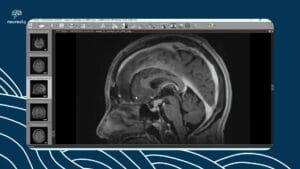

Embolização da artéria meníngea média para hematoma subdural crônico